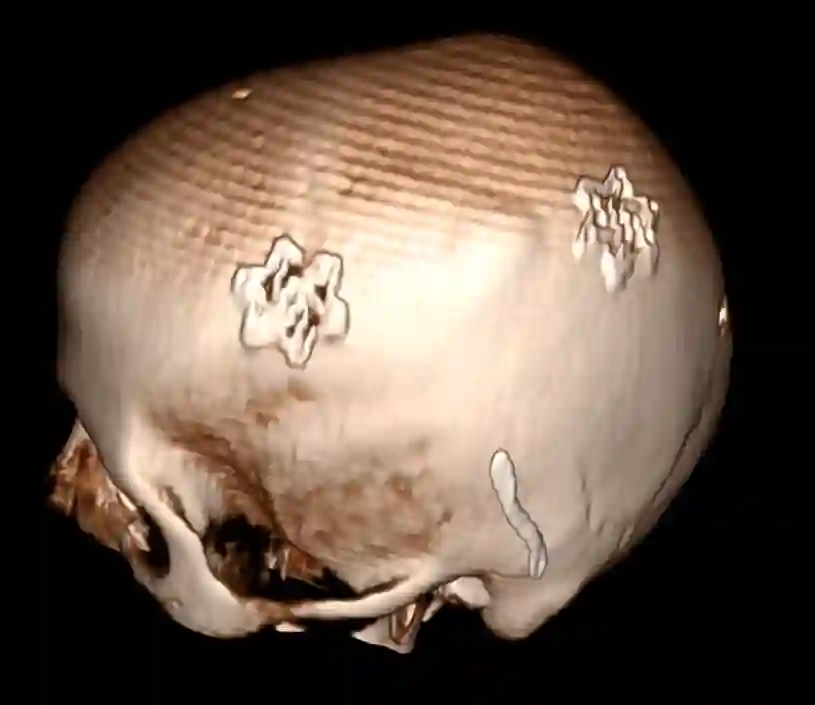

Bohrlochtrepanation

CT Rekonstruktion eines Patienten nach einer zweifachen Bohrlochtrepanation im Rahmen eines chronischen Subduralhämatoms. Auf den Bohrlöchern befinden sich zur Abdeckung Stryker low-profile Plättchen.